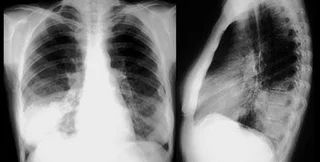

Главным источником воздействия искусственной радиации на человека являются медицинские исследования и процедуры. К такому выводу пришли эксперты Научного комитета ООН по действию атомной радиации

Согласно данным специалистов, на медицину приходится 98% радиационного облучения из искусственных источников.

Как сообщает радио ООН, с 1997 по 2007 год в мире каждый год проводилось в среднем 3,5 млрд. рентгенологических исследований. Это на 40% больше, чем в предыдущем десятилетии.

Несмотря на то, что диагностика и лечение с использованием радиации - шаг вперед в развитии медицины, МАГАТЭ и ВОЗ обеспокоены, что зачастую такие процедуры назначаются без достаточных оснований, а используемая доза облучения превышает допустимую. Причина, как правило - недостаточная квалификация медперсонала.